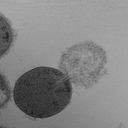

ExoLytics is a private, pre-clinical stage biotech startup targeting the global antimicrobial resistance (AMR) crisis. The company's innovative approach centers on engineering endolysins—enzymes that rapidly break down bacterial cell walls—as a new class of targeted, narrow-spectrum therapeutics intended to be alternatives to traditional antibiotics. Operating in a high-need, high-opportunity market, ExoLytics aims to develop disruptive solutions for drug-resistant infections, though it faces significant scientific, regulatory, and commercial challenges typical of an early-stage venture. The company appears to be pre-revenue and in the foundational research and platform development phase.

Engineered endolysin enzymes derived from bacteriophages, designed to precisely target and lyse drug-resistant bacterial pathogens.